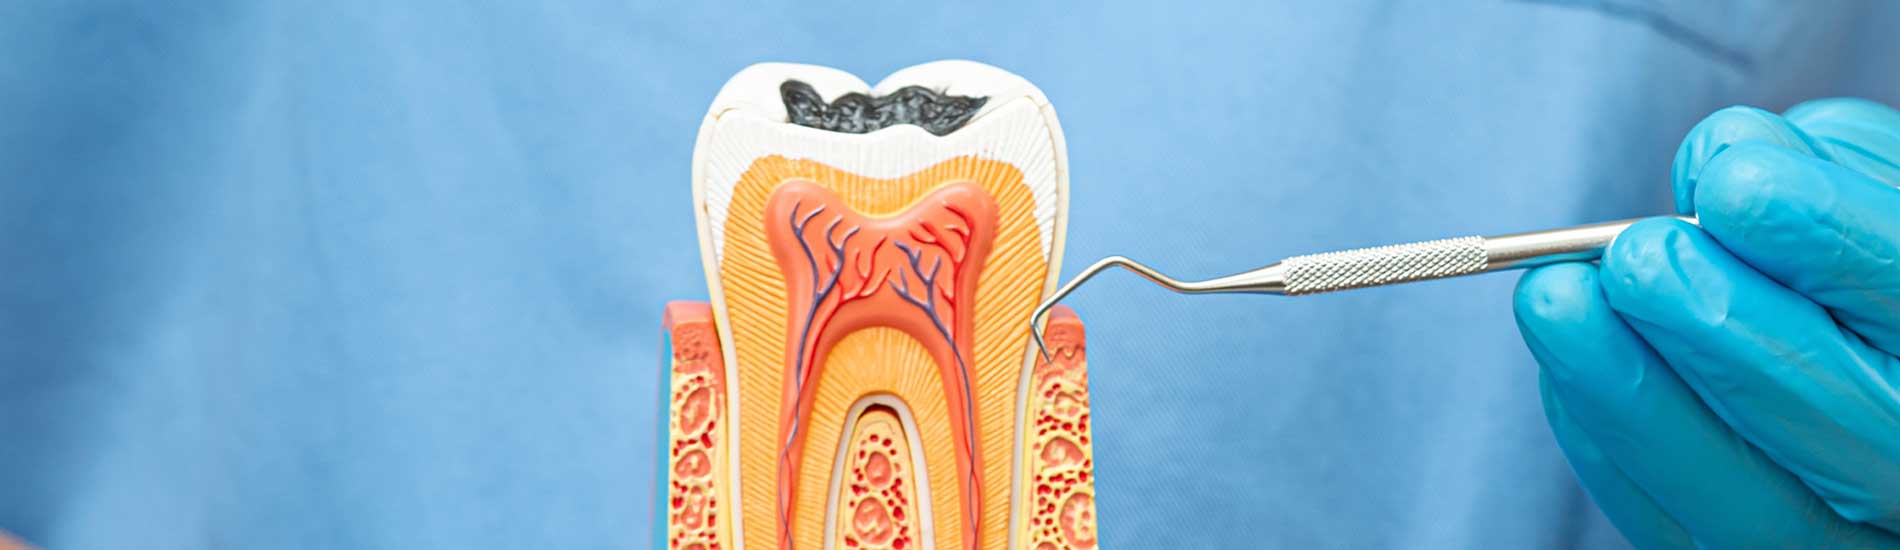

In family dentistry, root canal treatment is an essential procedure. This technique is required to preserve healthy teeth, even though it hurts. There are several causes for a patient to need root canal treatment. Every dentist aspires to refrain from conducting root canals unless a clear and immediate need exists. The likelihood of a tooth infection developing is decreased with root canal treatment, which also saves and maintains the tooth. Monarch Dentistry can conduct top-notch root canal treatment in Mississauga.

A root canal treatment is exactly what?

The inside of a tooth is made up of dental pulp. Blood vessels and other types of tissue that preserve the tooth's vitality make up the pulp. The unhealthy dentin inside the tooth is removed by the dentist during a root canal treatment. Numerous problems, including tumours and other difficulties, can result from infected dentin. The dentist will apply a temporary crown to the tooth after the pulp has been removed until a permanent crown can be made. This approach is quite typical.

Why do I need to get a root canal treatment?

When a tooth issue results in a pulp infection, Mississauga root canal therapy is used. This may be brought on by a cavity that has not been filled or a cracked filling that has enabled foreign objects to enter the tooth. Usually, you can tell when you need a root canal treatment because your tooth will hurt and you will be in a lot of pain.